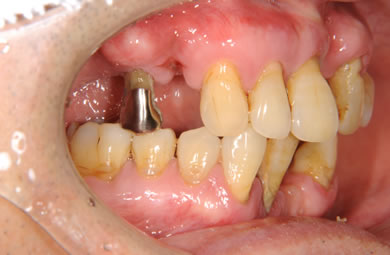

インプラントの症例写真 IMPLANT

骨再生スピードインプラント治療+AGC連結セラミック治療+セラミック治療

| 性別/年齢 | 男性 / 61歳 | ||||||||||||||||||||||||||||||||

| 主訴 | 歯周病の治療およびインプラント治療や義歯治療について相談したい。 | ||||||||||||||||||||||||||||||||

| 治療方針 | ソケットリフト法により上顎洞底部を拳上することにより、骨の無い部分に骨をつくってあげ、インプラント治療を可能にする。さらに歯周病により組織の破壊が著しいので、AGC連結セラミック治療により上顎の審美的回復を行う。 | ||||||||||||||||||||||||||||||||

| 治療内容 | インプラント7本(抜歯AGC即日スピードインプラント+ソケットリフト)、AGCハイブリッドセラミック連結ブリッジ1装置(上顎)ハイブリッドセラミック8本 | ||||||||||||||||||||||||||||||||